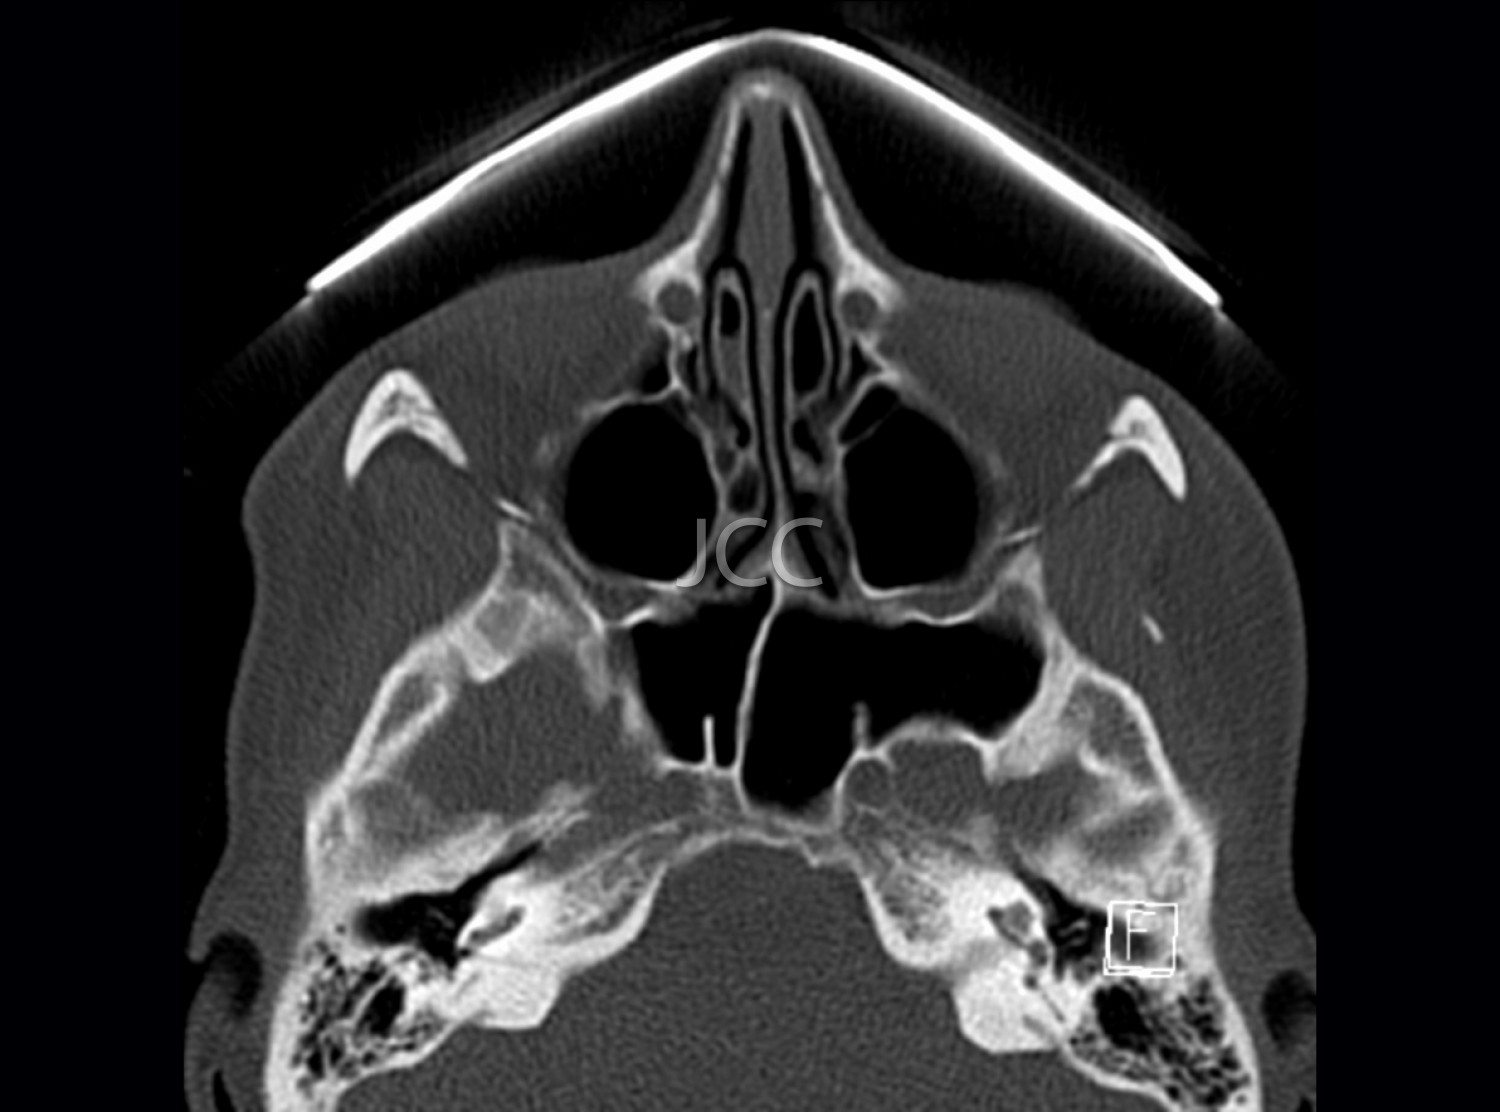

Tomografia Axial Computorizada - TAC Seios Perinasais

A Tomografia Axial Computorizada (TAC) - Dupla Energia - 256 cortes é uma técnica de diagnóstico que permite a avaliação de várias partes do corpo humano, incluindo pulmões, fígado, pâncreas, rins, coração, estruturas vasculares e estruturas ósseas.